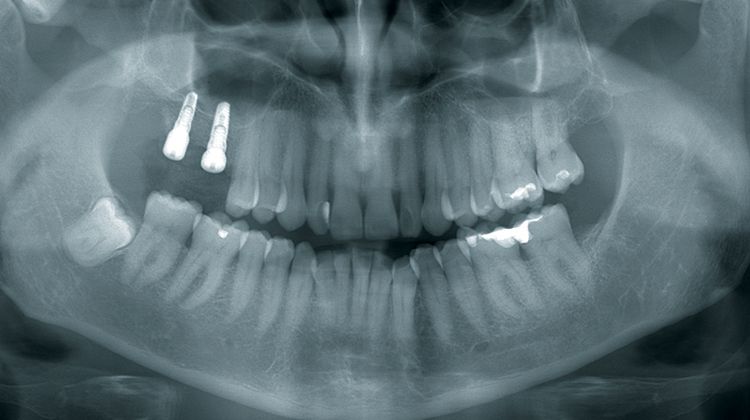

BACK: We work with our own DVT device. We make the image of the bone defect, discuss the situation with the patient and provide information about all the treatment alternatives - from allogeneic bone block to osteoplastic procedures like bone splitting. If the patient decides in favor of CAD/CAM-created allogeneic blocks, we send the DICOM data generated by us to the company which supplies this technology, in our case Botiss or Zimmer Dental. Here the three-dimensional bone block is designed.

BLUME: We concentrate on more complicated indications: Anterior tooth, posterior teeth region in the maxilla, difficult posterior teeth region in the mandible.

BLUME: For allografts, quite a few studies are already available, but the situation is still meager as regards the CAD/CAM created allografts. We have implanted almost 70 bone blocks in the last five years and are surprised ourselves at how stable the volume of the allogeneic blocks has remained, especially as regards the vertical height. And for us this is also one of the main arguments why we recommend this augmentation method so highly. Such constancy in the vertical axis is not offered by other bone replacement materials.